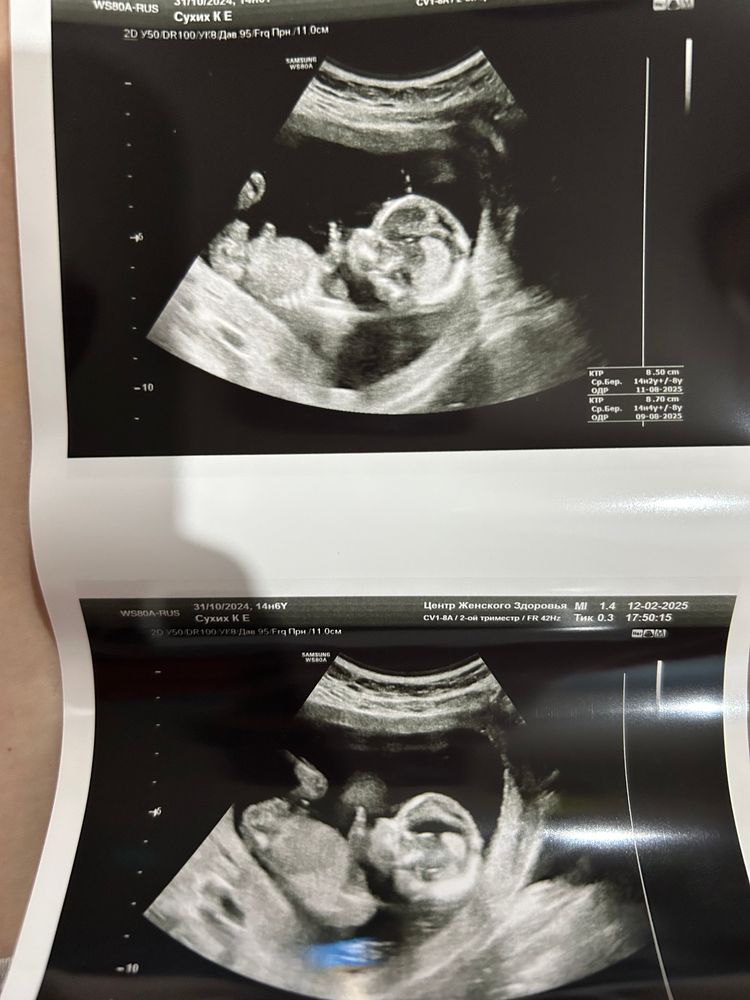

Девочка или мальчик ?)

Тут бугорка не видно, вижу пуповину. Но по темным точкам в зоне бугорка( попа и формирующееся влаг.) скажу, что девочка

Ну блин,серьезно думаете что бугорок который вы ищите,находится на животе,вместо пупка?🤓 Вам не кажется что это пуповина?🙈🤔 Вопрос не только к автору,но и к комментаторам.

Я не знаю, что торчит в районе животика, но бугорок вообще ниже располагается. И малыш закрыл его ножкой ☺️ Мне в 12 недель мальчика предположили, не ошиблись. Девочек чаще путают.

Тоже думаю, что мальчик) У нас тоже бугорок на таком сроке вверх был )

Мальчик

Кристина , бугорок вверх торчит) ну если это он

Кристина , нее, на таком срок еще половые органы не видны. И у мальчиков, и у девочек половые бугорки. По направлению бугорка и предполагают пол. Если прямо смотрит - то девчонка. А если вверх , как у Вас на фото, то парень.

Пол по УЗИ Пол на 17 неделе